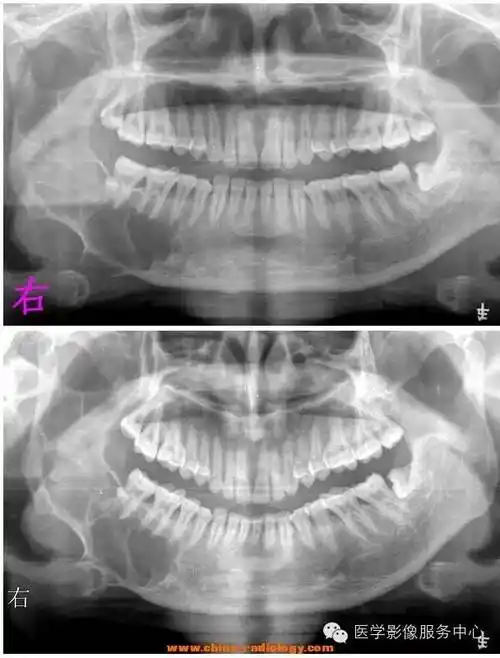

少见下颌骨成釉细胞15年后瘤颊部异位复发非本专勿进

下颌骨病例有病理病理结果造釉细胞瘤

【病例】下颌骨造釉细胞瘤1例x线及ct影像表现